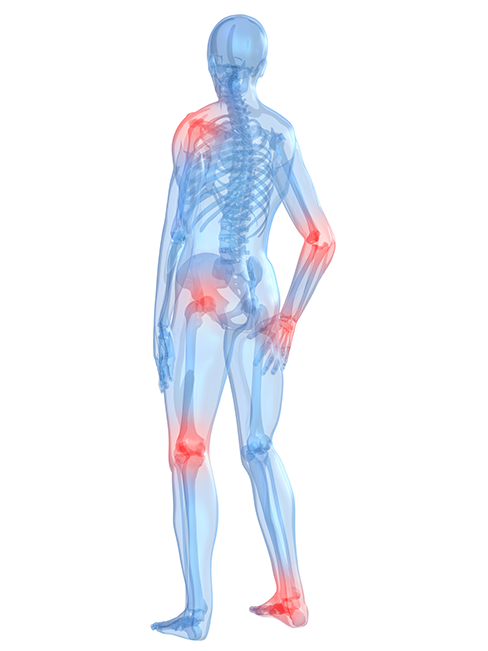

Chez InterMD, notre engagement est de comprendre vos besoins, soulager vos douleurs et améliorer votre qualité de vie.

Les troubles musculosquelettiques sont fréquents et souvent très incommodants. Ils représentent une part importante des consultations médicales.

À la clinique médicale InterMD, nous avons développé une expertise spécifique dans leur prise en charge. Comme les causes de douleur peuvent être nombreuses, un diagnostic précis est essentiel pour orienter vers le traitement le plus approprié.